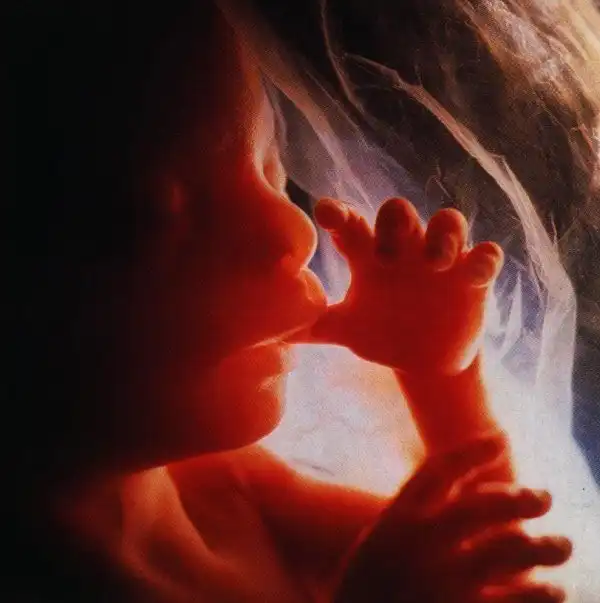

У мамы в животике)